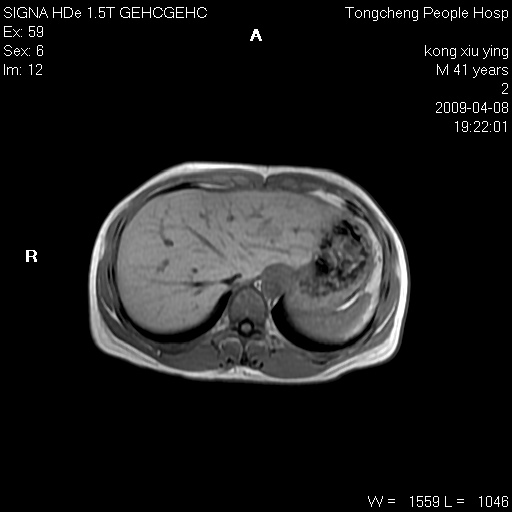

标题: CL1008:【经典】胆囊石榴籽样结石。

女,41岁。健康体检——彩超提示:胆囊显示不清。平素健康,无不适感。

腹部mr扫描及mrcp,图像如下: